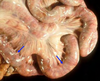

What is this tissue? What is its function?

This is the esophagus of a leatherback sea turtle

Function: facilitate swallowing of prey - prevents regurg